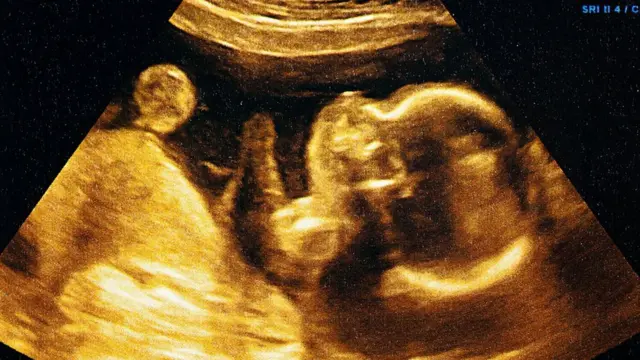

Fuente de la imagen, iStock/Getty Images

Los primeros 120 días

"Hay una posición más abierta al aborto en las primeras fases. La cuestión fundamental que discuten los expertos, los juristas y los teólogos musulmanes es: en qué momento se pasa de un conjunto de células a constituirse en un ser humano", le explica a BBC Mundo Delfina Serrano, investigadora del Departamento de Estudios Judíos e Islámicos del Instituto de Lenguas y Culturas del Mediterráneo y Oriente Próximo de España.

Según El Mushtawi, la fe musulmana cree que después de 120 días se forma el ser humano.

"Después de 120 días, Dios le envía el ángel para insuflarle el alma o el espíritu (al embrión)", explica el especialista. "Desde la propia concepción del ser humano hasta su muerte, una vez es insuflado el espíritu o el alma en el feto, la vida comienza para nosotros, los musulmanes".

Hay algunos sabios que sostienen que hasta los 120 días, se puede interrumpir el embarazo si la vida de la madre está en riesgo", agrega.

Pero si una vez pasado ese periodo, la vida de la madre está en peligro, el aborto debe permitirse, de acuerdo con la unidad de Religión y Ética de la BBC.

Así, algunas escuelas de pensamiento islámico permiten el aborto en las primeras 16 semanas del embarazo, pero otras, más conservadoras, solo lo aceptan en las primeras 7 semanas.

Según la división Religión y Ética de la BBC, si se confirma que en la etapa temprana de un embarazo el feto sufre de un defecto que no puede ser tratado y que le causará un gran sufrimiento, un grupo de académicos musulmanes diría que el aborto debe ser permitido, siempre y cuando el embarazo no haya llegado a los 120 días.

Una opinión un poco más liberal indica que un aborto dentro de los primeros 120 días sería permitido si el niño naciera con una deformidad física y mental tal que estaría privado de llevar una vida normal. La opinión de al menos dos expertos médicos es imprescindible en ese caso.